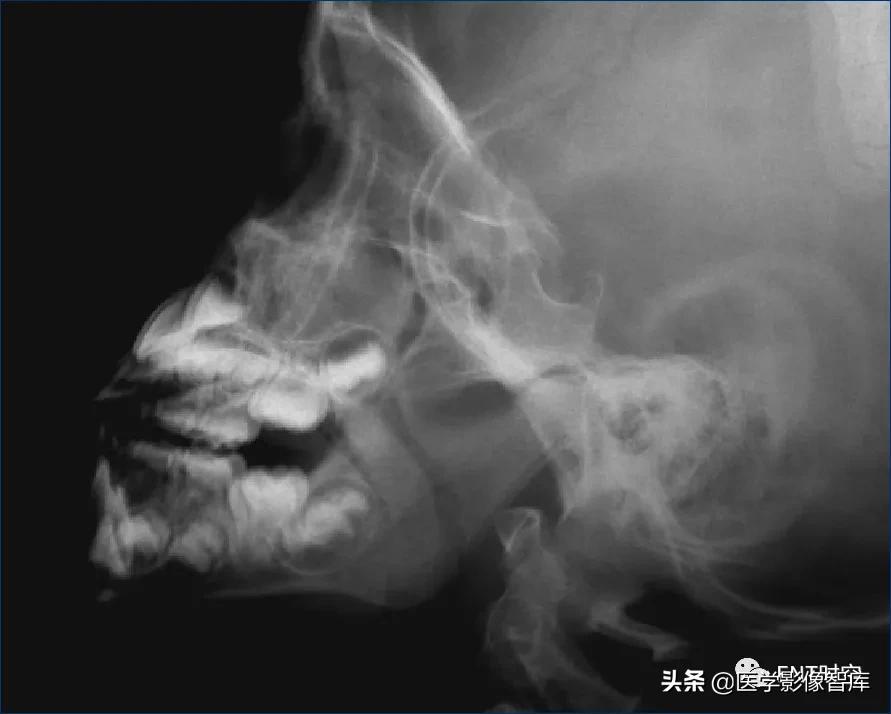

腺样体-鼻咽腔比率A/N值:

腺样体厚度(A)的测量:

腺样体最突点至枕骨斜坡颅外面的垂直距离

>13mm,就会出现鼻咽腔气道变窄,甚至闭塞。

(1)1987年Elwany提出鼻咽腔的宽度(N)测量方法:

硬腭后端--翼板与颅底交点间距

(2)鼻咽腔的宽度(N)测量方法:

N为腺样体最凸部鼻咽腔的宽度,即垂线的反向延长线与硬腭后端或软腭前中部上缘的交点和枕骨斜坡颅外面切线的垂直距离。

A/N参考值:

- 儿童在2~12岁腺样体有生理性肥大,故腺样体在儿童生长的不同年龄的生理变化,提出

- A/N比值:

- 0.5-0.6 正常

- 0.61-0.70 中度肥大

- >0.70 病理性肥大

- >0.80 显著肥大